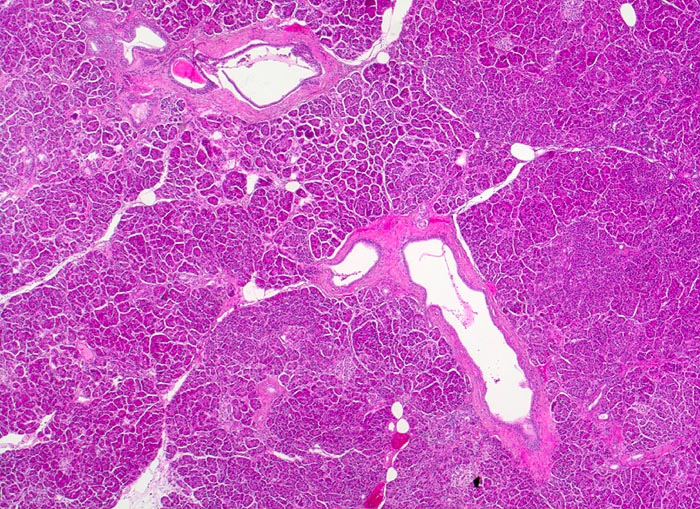

PathoPic – image database / PathoPic ID 4262 - Normales exokrines Pankreas

Normales exokrines Pankreas

Pankreas

Das Pankreas ist von einer dünnen Kapsel umgeben, von der aus schmale bindegewebige Septen in das Parenchym eindringen und zu einer Lobulierung führen. In den Septen verlaufen die Ausführgänge des exokrinen Pankreas. Die einzelnen Läppchen bestehen aus mehreren Azini (=mehrere Azinuszellen gruppiert um zentroazinäre Zellen überleitend in ein Schaltstück).

Vergrösserung

25